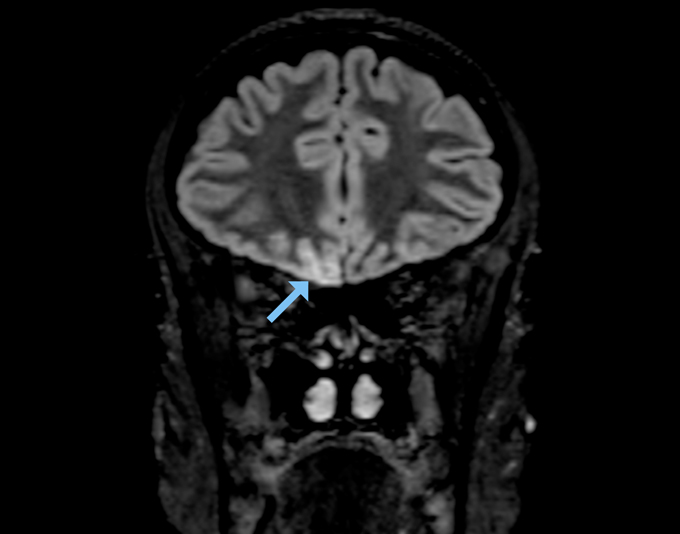

But an MRI of a young woman’s brain turned up signs of SARS-CoV-2 infection in several areas involved in smell, including the olfactory bulb and a part of the brain called the right gyrus rectus, which helps process smell signals, scientists report May 29 in JAMA Neurology. The woman, who worked as a radiographer in a ward treating COVID-19 patients, had completely lost her sense of smell, but had only mild symptoms otherwise. Based on these findings, Letterio Politi, a radiologist at Humanitas Clinical and Research Hospital and University in Milan, Italy, and colleagues suspect that the virus moved into the woman’s brain from her nose.